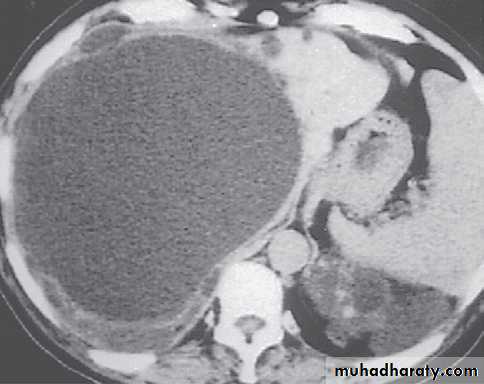

MRI images of kidneys. A Normal kidneys. B Polycystic kidneys; although the kidney enlargement is extreme, this patient had only slightlyreduced GFR.

Markedly enlarged polycystic kidneys in comparison to a normal kidney in the middle.